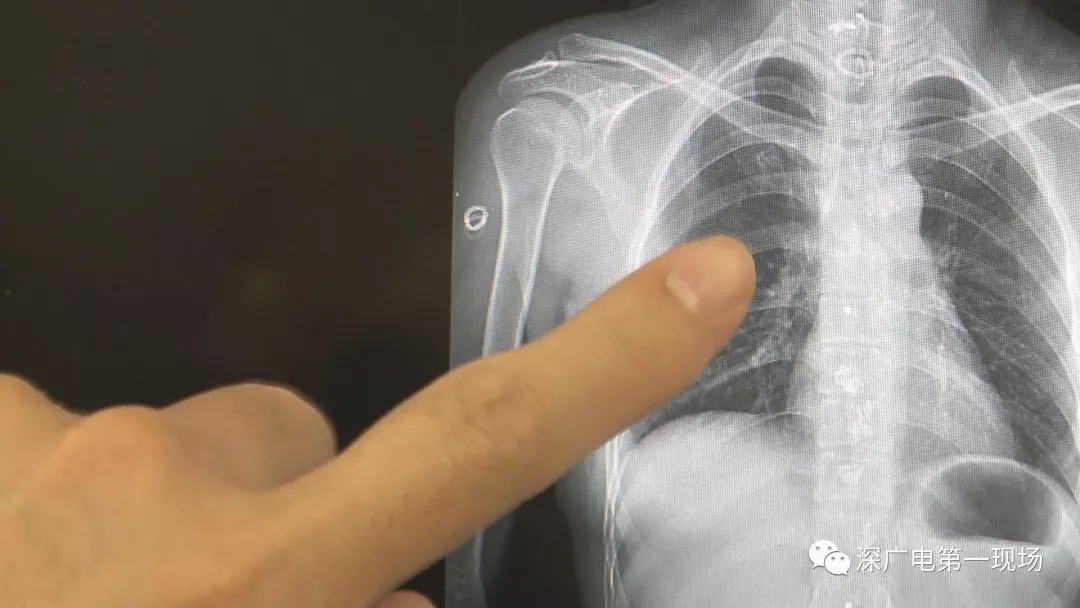

深圳一女子全身被植入彈簧圈,數(shù)量多到驚人!竟是為治這病…

經(jīng)醫(yī)院常規(guī)檢查后發(fā)現(xiàn)

為了治病

這位病人竟然在全身

被植入了大!量!彈!簧!

數(shù)量多到無!法!計(jì)!數(shù)!